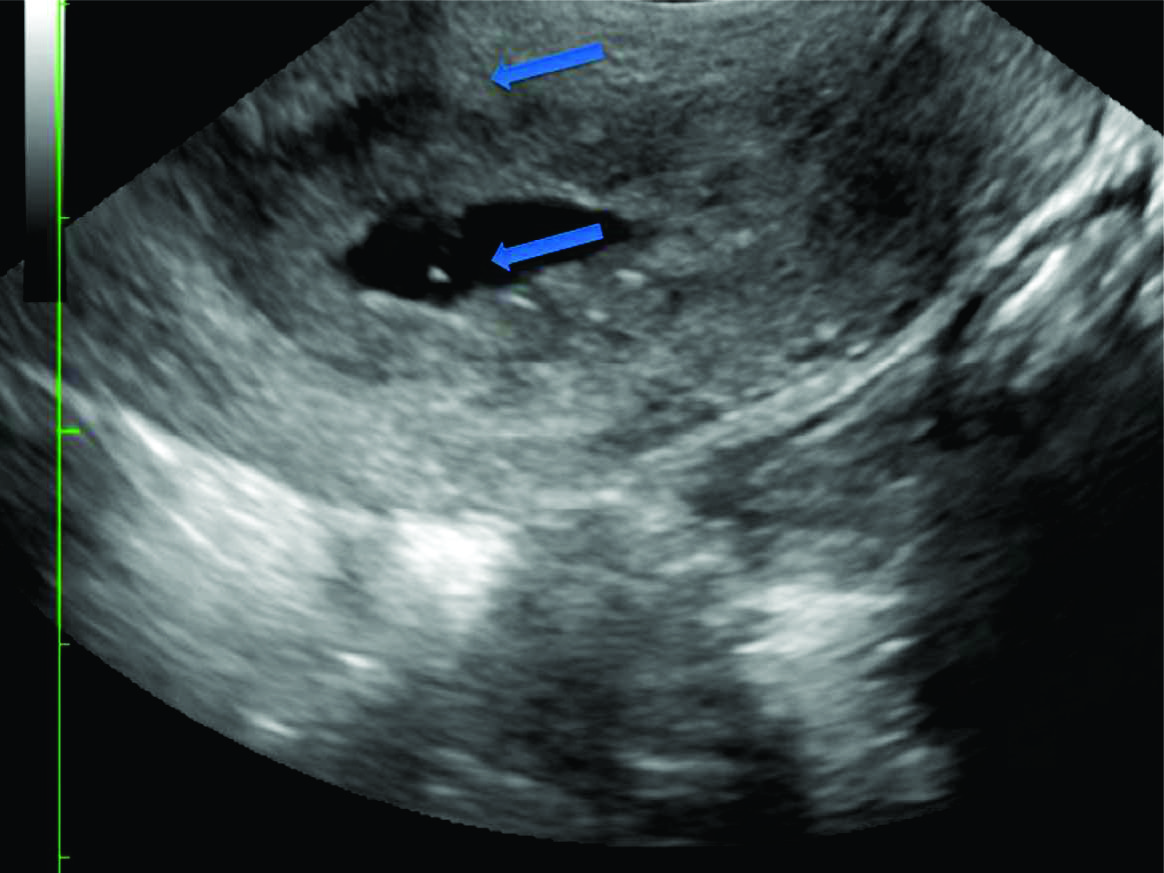

Figura 2

Ecografía trans vaginal evidenciando útero en el plano sagital.

Se observa saco gestacional a nivel cervical (flecha gruesa), y orificio cervical interno cerrado (flecha fina). El endometrio está engrosado.